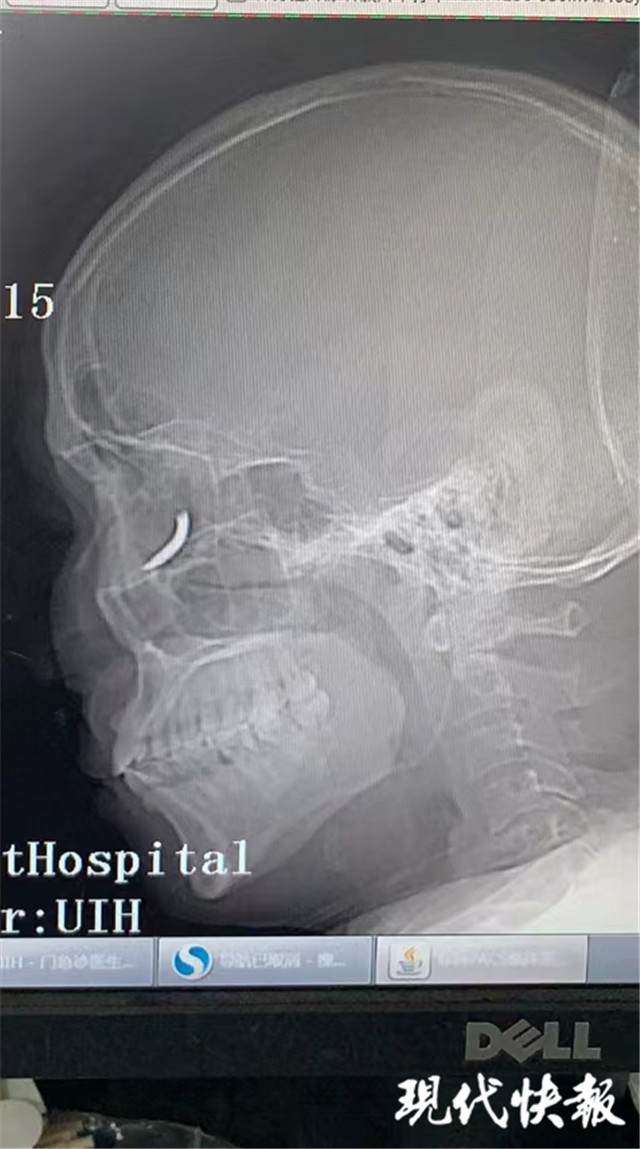

(通訊員 孫忠河 記者 梅書(shū)華)鐵釘扎入眼眶,卻不疼不癢,這是怎么回事?三天前,王師傅在溧水的建筑工地干活時(shí),突然感覺(jué)有異物進(jìn)入眼內(nèi),但沒(méi)當(dāng)回事,后來(lái)出現(xiàn)頭暈才就診,沒(méi)想到是鐵釘扎入了眼眶。南京市第一醫(yī)院醫(yī)生通過(guò)半小時(shí)手術(shù),順利將一根長(zhǎng)約一公分的鐵釘取出。

“當(dāng)時(shí)在敲鐵釘,感覺(jué)什么東西進(jìn)眼睛里了,但沒(méi)影響視力,還以為是水泥灰之類(lèi)的。”三天前,王師傅眼中進(jìn)入異物,感覺(jué)頭暈不適后,去當(dāng)?shù)蒯t(yī)院就診,拍了X光片后,竟然發(fā)現(xiàn)自己眼眶內(nèi)有一個(gè)鐵釘樣的異物。

隨即,王師傅趕到南京市第一醫(yī)院眼科就診,眼科門(mén)診曹雪倩醫(yī)生接診后,立即完善CT等相關(guān)檢查。剛準(zhǔn)備休息的眼科醫(yī)生范偉杰,立即與副主任醫(yī)師趙貴陽(yáng)聯(lián)合研究這個(gè)特殊的病例。專(zhuān)家們發(fā)現(xiàn)這枚鐵釘不偏不倚正好扎進(jìn)病人的眼眶里,但是眼眶內(nèi)解剖結(jié)構(gòu)復(fù)雜,要在盡可能保護(hù)正常組織結(jié)構(gòu)的情況下完成探查并取除鐵釘,手術(shù)難度較大。

范偉杰與趙貴陽(yáng)反復(fù)討論后,制定了詳細(xì)周密的手術(shù)方案,最終以局麻下、眼袋美容切口進(jìn)入,順利取出了一根長(zhǎng)約一公分的鐵釘。整臺(tái)手術(shù)耗時(shí)半小時(shí),手術(shù)過(guò)程中沒(méi)有損傷到眼球壁和視神經(jīng),但醫(yī)生發(fā)現(xiàn)因?yàn)殍F釘?shù)那秩?,視網(wǎng)膜周邊有出血,所以做了視網(wǎng)膜光凝。術(shù)后視力1.0,面部看不出瘢痕。王師傅的眼球終于安全保住了。